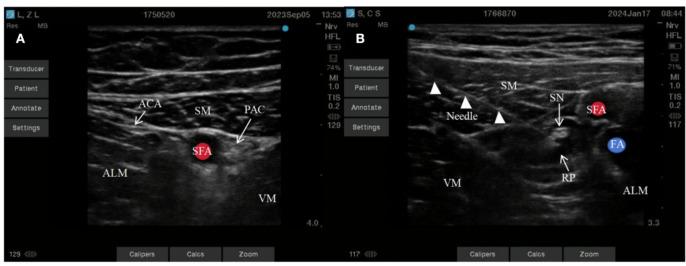

To explore the impact of ultrasound-guided proximal adductor canal and pes anserinus tendon block on early recovery after anterior cruciate ligament reconstruction surgery via daytime knee arthroscopy. A total of 127 patients, aged 18-60 years, with ASA class I-II, undergoing anterior cruciate ligament reconstruction via knee arthroscopy under general anesthesia with laryngeal mask airway intubation, were selected. These patients were randomly divided into three groups: Group C (43 cases), Group N (41 cases), and Group N (43 cases). Control group C: received proximal block of the adductor canal with 0.5% ropivacaine (15 ml); Experimental group N: received proximal block of the adductor canal combined with tendon block of the pes anserinus with 0.5% ropivacaine (15 ml per site); Experimental group N: received proximal block of the adductor canal combined with tendon block of the pes anserinus with 0.5% ropivacaine plus 5 mg dexamethasone (15 ml per site). Record the VAS scores at each time point after awakening, 3 h after surgery, 6 h after surgery, 12 h after surgery, 24 h after surgery, 48 h after surgery, and 72 h after surgery during rest and knee flexion activities of the knee joint. Record the quadriceps muscle strength after awakening, Ramsay sedation score after awakening, time of first ambulation after surgery, and the amount of sufentanil, propofol, and remifentanil used during the operation. Record the amount of tramadol and flurbiprofen axetil added postoperatively. Record the anxiety scores and rapid eye movement sleep behavior disorder scores before and 3 days after surgery. Record the occurrence of breakthrough pain and adverse reactions 3 days after surgery. Compared with Group C, both Group N and Group N showed significantly lower rest and activity VAS scores at all time points on postoperative day 3 (P < 0.05), earlier time to first ambulation after surgery (P < 0.05), significantly lower HADS-A scores and sleep scores on postoperative day 3 (P < 0.05), significantly higher Ramsay sedation scores after awakening (P < 0.05), and significantly reduced use of additional tramadol and flurbiprofen axetil after surgery (P < 0.05). The intraoperative sufentanil dosage was also significantly reduced (P < 0.05). There were no statistically significant differences in quadriceps muscle strength and adverse reactions during the awakening period among the three groups (P > 0.05). Ultrasound-guided proximal adductor canal and pes anserinus tendon block (15 ml of 0.5% ropivacaine each) can effectively alleviate pain 3 days after anterior cruciate ligament reconstruction surgery under knee arthroscopy, with good analgesic effects, and has minimal impact on quadriceps muscle strength after awakening, promoting early postoperative ambulation; at the same time, this blocking method can reduce the occurrence of postoperative anxiety and sleep disorders.

探讨超声引导下股内收肌管近端及鹅足肌腱阻滞对日间膝关节镜下前交叉韧带重建术后早期恢复的影响。选取127例年龄在18 - 60岁、ASA分级为I - II级、在喉罩气道插管全身麻醉下行膝关节镜下前交叉韧带重建术的患者。将这些患者随机分为三组:C组(43例)、N组(41例)和N组(43例)。对照组C:采用0.5%罗哌卡因(15 ml)行股内收肌管近端阻滞;实验组N:采用0.5%罗哌卡因(每部位15 ml)行股内收肌管近端阻滞联合鹅足肌腱阻滞;实验组N:采用0.5%罗哌卡因加5 mg地塞米松(每部位15 ml)行股内收肌管近端阻滞联合鹅足肌腱阻滞。记录患者苏醒后、术后3 h、6 h、12 h、24 h、48 h及72 h在膝关节休息及屈曲活动时各时间点的视觉模拟评分(VAS)。记录患者苏醒后的股四头肌肌力、苏醒后的Ramsay镇静评分、术后首次下床活动时间以及术中使用的舒芬太尼、丙泊酚和瑞芬太尼的用量。记录术后追加曲马多和氟比洛芬酯的用量。记录术前及术后3天的焦虑评分和快速眼动睡眠行为障碍评分。记录术后3天爆发性疼痛及不良反应的发生情况。与C组相比,N组和N组在术后第3天各时间点的休息及活动VAS评分均显著降低(P < 0.05),术后首次下床活动时间更早(P < 0.05),术后第3天的医院焦虑抑郁量表 - 焦虑(HADS - A)评分和睡眠评分显著降低(P < 0.05),苏醒后的Ramsay镇静评分显著升高(P < 0.05),术后追加曲马多和氟比洛芬酯的用量显著减少(P < 0.05)。术中舒芬太尼用量也显著减少(P < 0.05)。三组患者苏醒期股四头肌肌力及不良反应差异无统计学意义(P > 0.05)。超声引导下股内收肌管近端及鹅足肌腱阻滞(各15 ml 0.5%罗哌卡因)可有效缓解膝关节镜下前交叉韧带重建术后3天的疼痛,镇痛效果良好,对苏醒后股四头肌肌力影响极小,促进术后早期下床活动;同时,该阻滞方法可减少术后焦虑及睡眠障碍的发生。